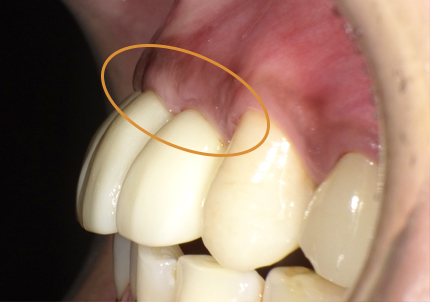

23.自然な形態のインプラント歯頚部

適切な治療計画と治療技術を有することで、このような自然な形態のインプラント歯頚部を形成することができます。

前歯の受傷前の歯肉の膨らみが、抜歯後にも変わらない状態を維持してインプラント治療されています。患者様、術者も結果がとても良いと満足しています。